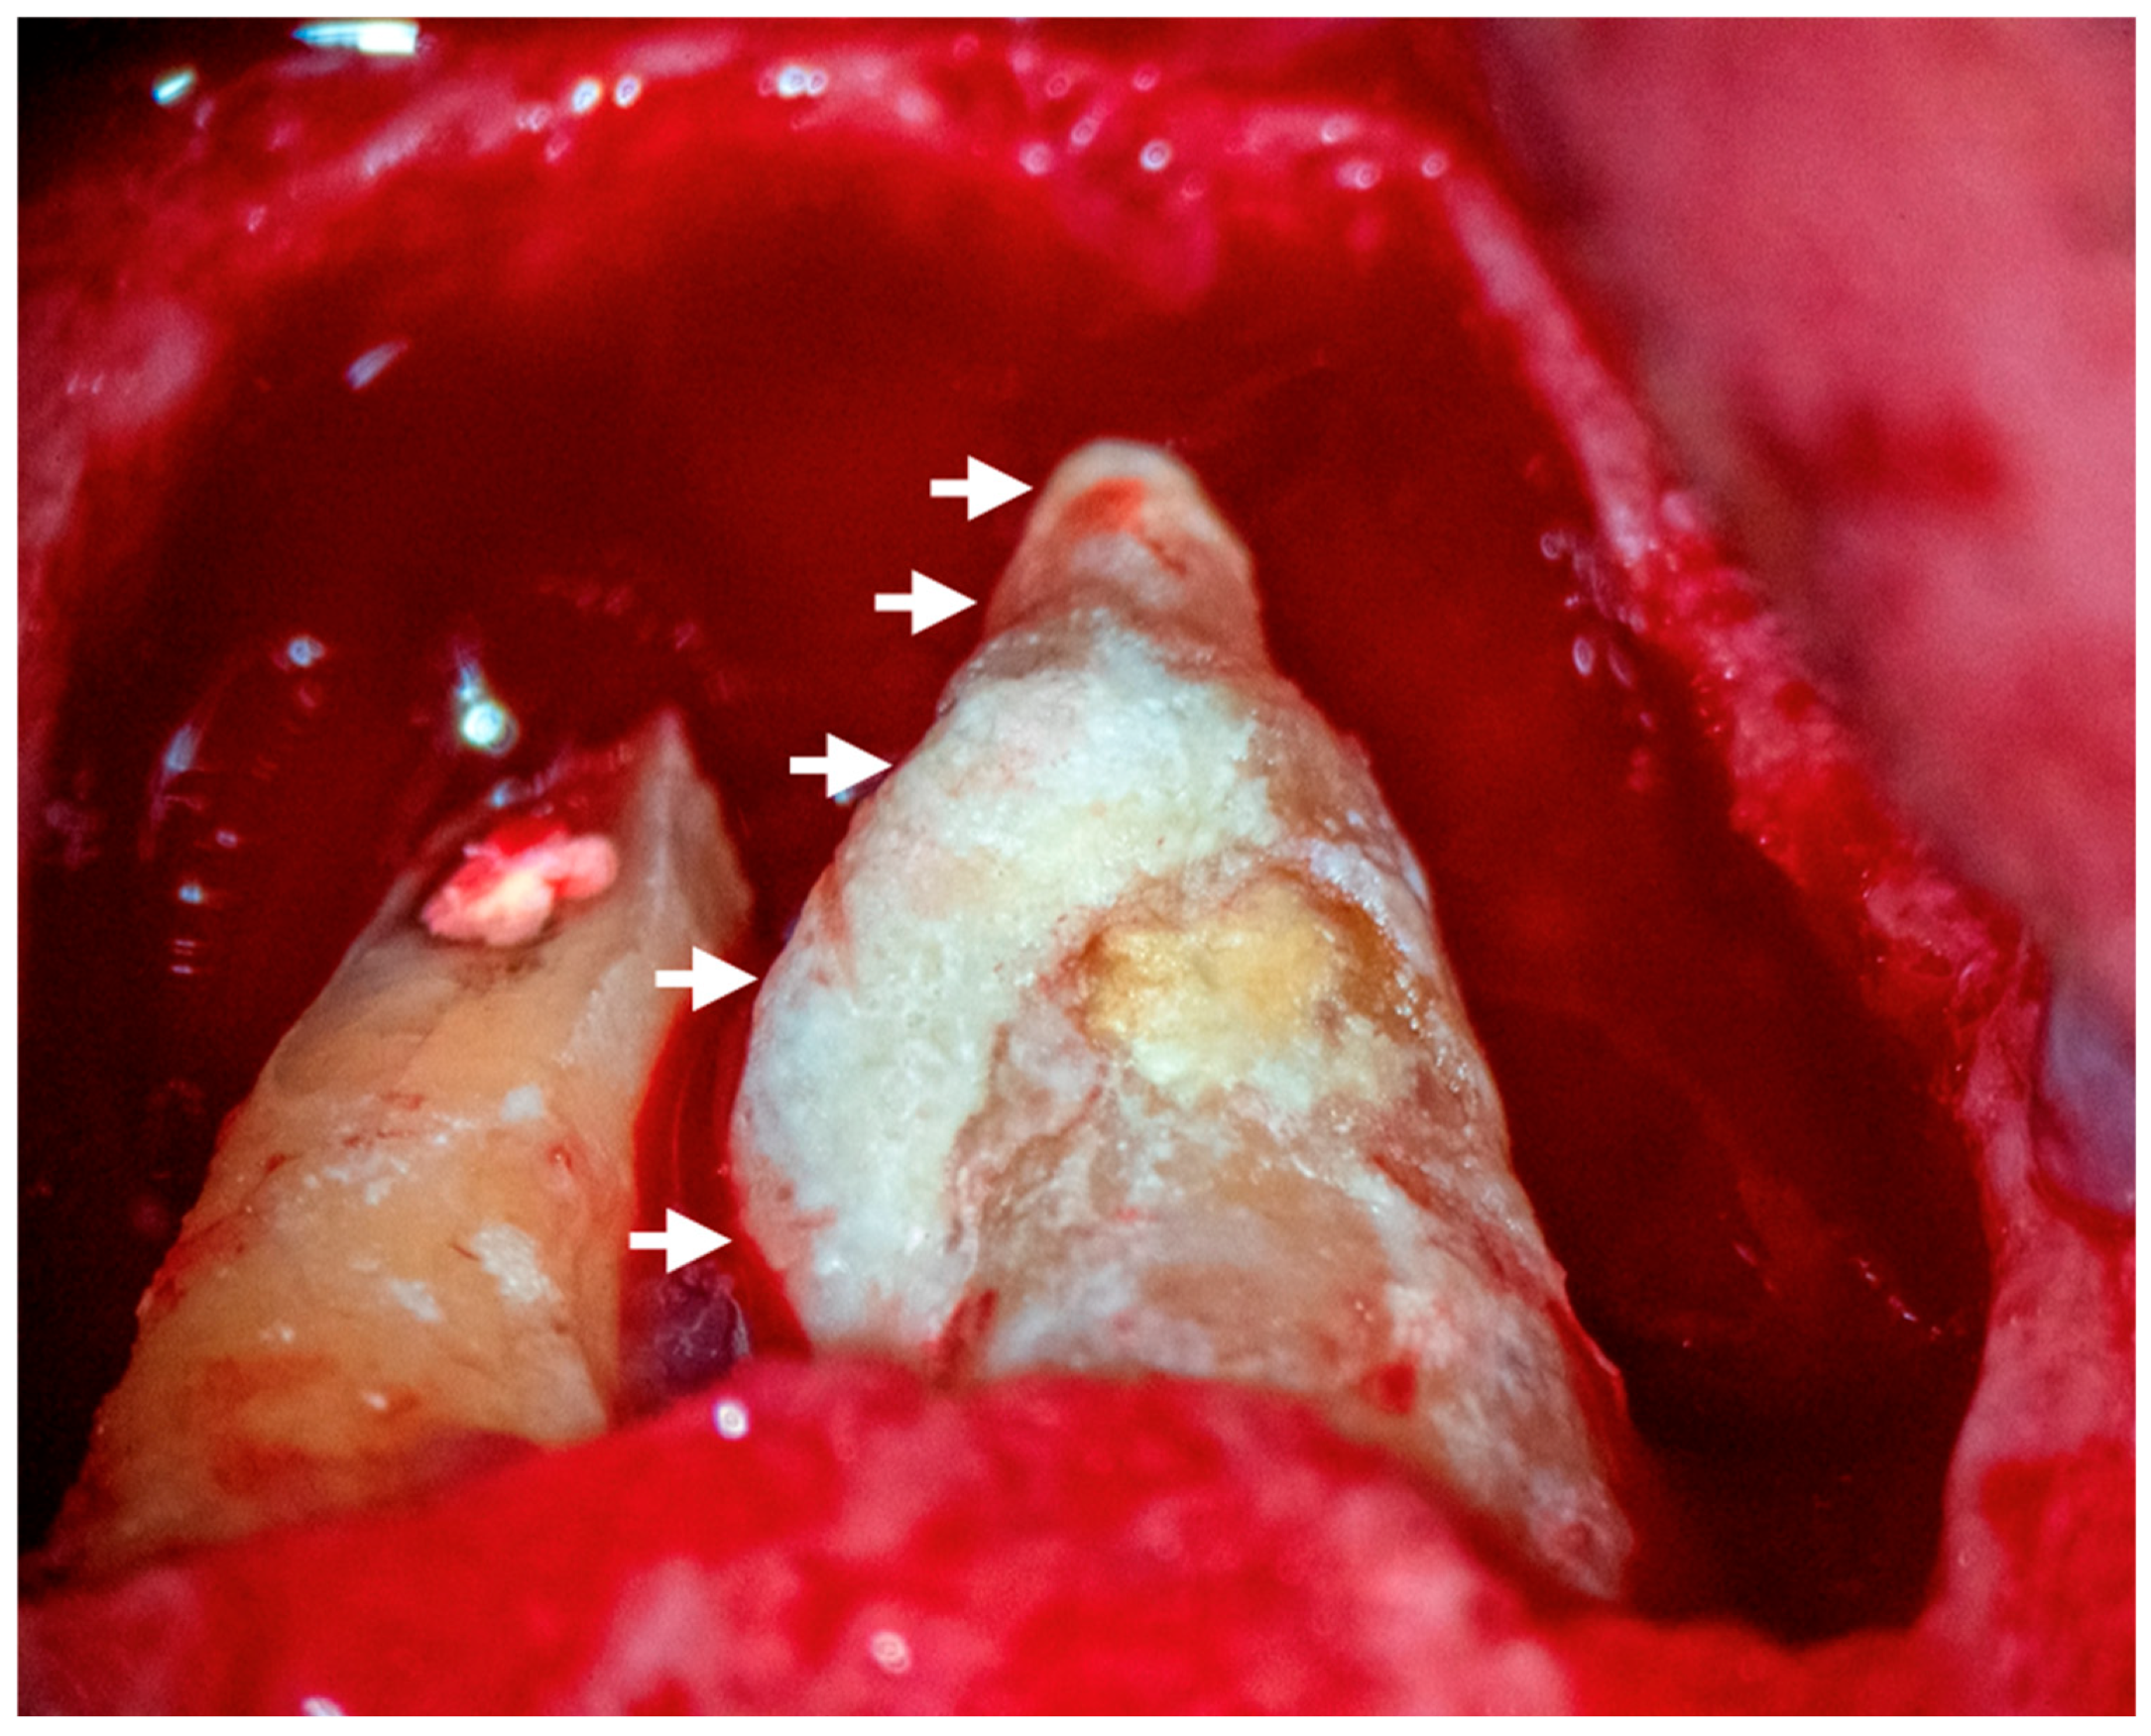

3.1.4. Extraradicular Biofilm and Calculus Formation

- Ricucci, D.; Candeiro, G.T.; Bugea, C.; Siqueira, J.F., Jr. Complex Apical Intraradicular Infection and Extraradicular Mineralized Biofilms as the Cause of Wet Canals and Treatment Failure: Report of 2 Cases. J. Endod. 2016, 42, 509–515. [Google Scholar] [CrossRef]

- Ricucci, D.; Martorano, M.; Bate, A.L.; Pascon, E.A. Calculus-like deposit on the apical external root surface of teeth with post-treatment apical periodontitis: Report of two cases. Int. Endod. J. 2005, 38, 262–271. [Google Scholar] [CrossRef]